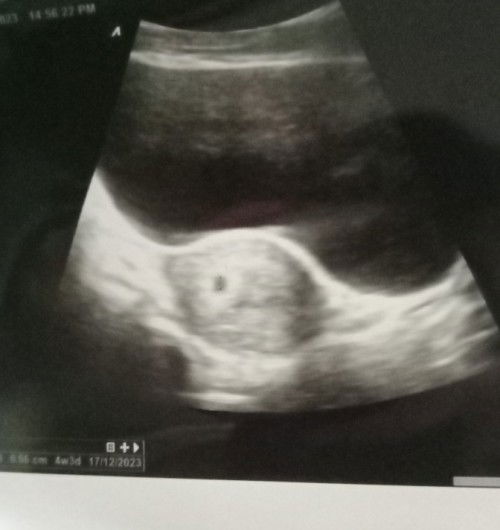

Bun, mau tanya, disini kira² ada ga ya..yg punya list pertanyaan ke obgyn klo pas jadwal USG? Kalau ada, mohon sharingny ya bun🙏 aku baru pertama hamil, jd bingung harus tanya apa aja.. Jangan rujak aku ya 🙏 Skrg aku 9w sebelumnya udh pernah usg, dan dokter bilang perkembangannya bagus. Aku pgn nanya nanya, tp bingung apa yg harus diajukan🙏#seriusnanya #ingintahu #firstmom #pleasehelp